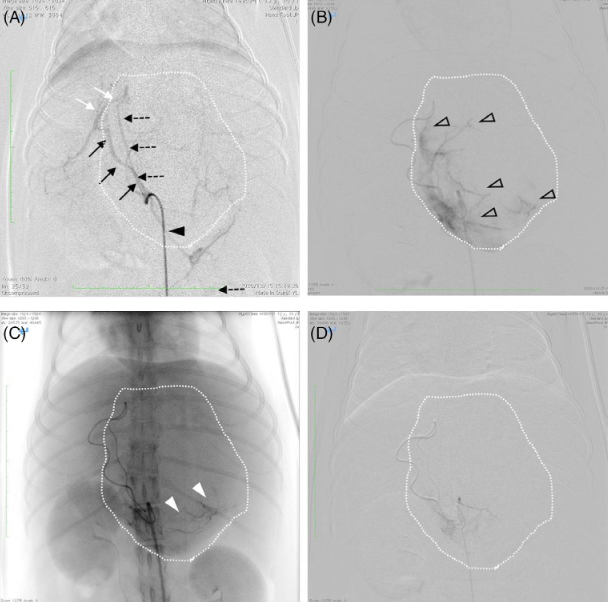

최근에 개에서 발생하는 간종양의 치료 옵션으로 인터벤션 방법이 많이 이용되고 있다.

원리는 간단한게 정상적인 간조직은 동맥에서 혈액의 20%를 받고, 문맥에서 80%의 혈류를 받는 반면

종양 조직은 정상과는 반대로 동맥에서 혈액의 80%를 받고 문맥에서 20%를 받는 현상을 이용하는 방법이다.

즉, 종양이 있는 간 부위로 가는 동맥을 막아버리면 정상조직은 혈액의 20%를 못받아 좀 괴롭기만 하겠지만

종양조직은 혈액의 80%를 받지 못해 괴롭고도 힘들어질거란 것이다.

동시에 세포 손상을 20% 이상 주는 항암제를 같이 투약했다면 간세포를 사멸시킬 수도 있을것이라는 원리로 사용되는게 인터벤션이다.

14마리지만 예후 평가를 한 논문이 새로 나와서 소개한다.

중위 생존기간이 419일이니 상당히 준수한 치료 효율이라고 생각되며

복강내 출혈이 있는 경우 생존상이 낮고, 종양의 크기가 원래 매우 컸다면 예후가 불량하다는 결과를 보여준다.

어쩌면 너무 당연하게 너무 커지기 전에 시술하는게 더 생존성이 높다는 말이니 주춤 하지 말고 바로 시행하는게 답이라고 보인다.